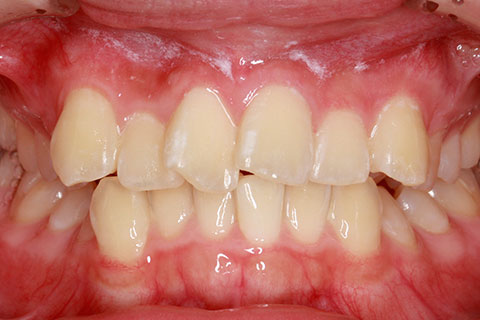

• オールセラミックの症例2

治療前

治療後

年齢・性別

45歳男性

治療期間

2ヶ月

抜歯

なし

治療費

70.4万円

備考

前歯8本の歯列不正によるセラミック治療

治療内容

歯質を削除し、セラミック冠をセメント合着

施術の副作用(リスク)

知覚過敏、歯髄炎、荷重負担